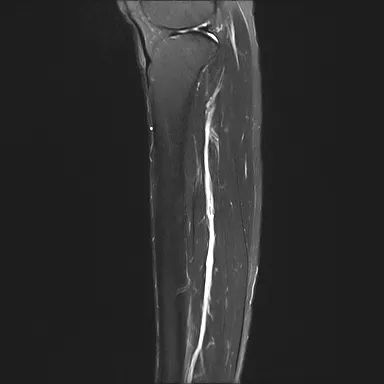

经复大专家团队会诊后,考虑到肿瘤离神经太近,实施冷冻消融可能会损害腿部神经,从而造成行动不便,故不适宜做冷冻消融术。专家提议以碘粒子(I-125)植入术进行治疗,降低手术的风险。和约翰进一步解说后,于2018年4月2日由周亮医生主刀行左小腿骨肉瘤碘粒子(I-125)植入治疗,手术准备就绪后,在CT、超声等影像引导下,在左侧胫骨肿瘤上植入16粒碘粒子(I-125),可对肿瘤组织进行持续性杀伤,同时减少对周围正常组织的损伤,避免损伤腿部神经。手术非常成功且术后未发现不良反应。

2018.07.05

2019.11.11

由于长期吸烟已致双肺“锈迹斑斑”,约翰于2018年4月7日在我院行右肺转移瘤氩氦刀冷冻消融术,首先通过2根冷冻针粘住肿瘤,对大肿瘤进行冷冻消融。其次,于2018年4月12日行左小腿骨肉瘤并双肺转移瘤介入化疗(吉西他滨+顺铂)。术后两个月左小腿骨肉瘤缩小60%,由最初的11cm缩小至4~5cm。2018年7月11日行左小腿肿物碘粒子(I-125)植入治疗(15粒);2018年12月5日发现右肺转移瘤冷冻消融术后新增周围渗出性病变,新增左下肺炎性病变可能;为消灭肿瘤,于2019年11月14日行右肺转移瘤氩氦刀冷冻消融术,现在骨肉瘤基本消失。约翰竖起大拇指道:“我曾听闻中国商业很发达,没想过中国医疗技术也如此先进,与中东国家和欧洲国家的单一性治疗不同,这里有各种的综合治疗方案适合病人,我认为复大肿瘤医院对于肿瘤病人来说是一个很好的机会,在这里治愈癌症的可能性很大。”